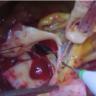

This is a highly novel way for performing an aortic root replacement, where the aorta is opened but not resected, and the coronary buttons are not harvested. Instead, the valsalva root graft is placed into the aortic annulus, and the coronary arteries are then sutured to the graft in situ without cutting the wall of the aorta.